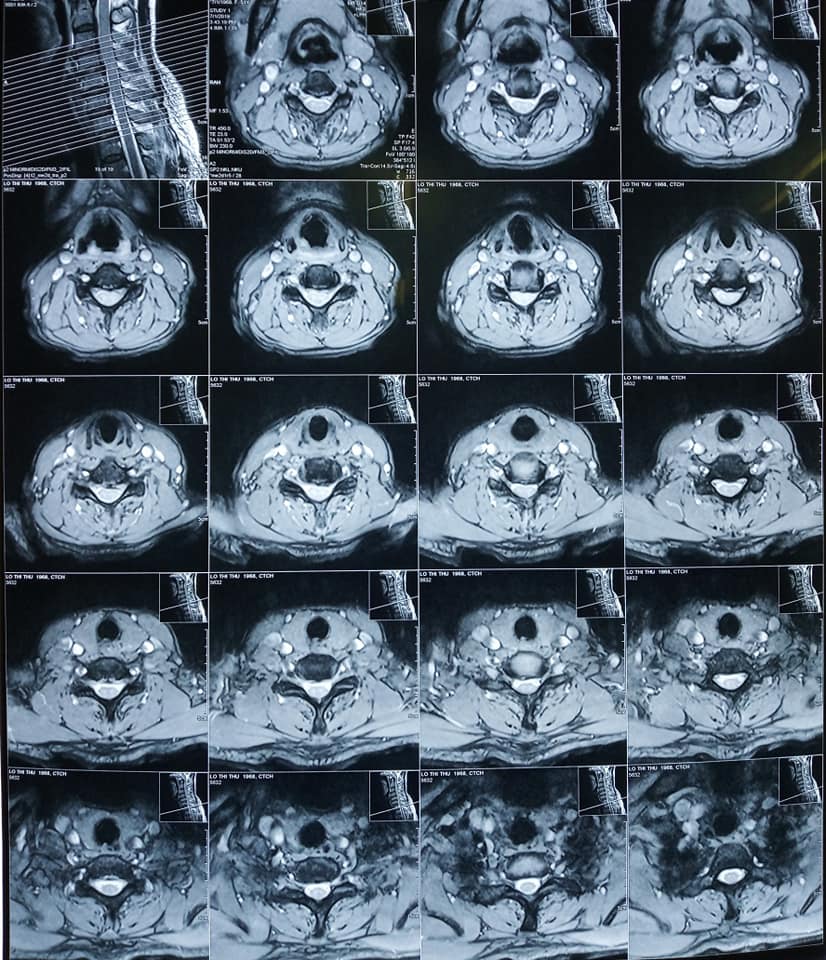

Sau khi được bác sĩ thăm khám, bệnh nhân được chẩn đoán bị Thasit vị đĩa đệm cột sống cổ C4C5 C5C6 và phù tủy cổ ngang mức C5.

Hình ảnh Phim chụp tình trạng :